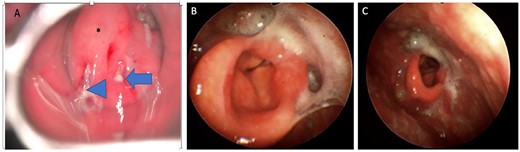

A 72-year-old man with diabetes presented to the emergency department with dyspnea, stridor and odynophagia that suddenly started 3 h earlier. Clinical examination revealed that the patient was febrile with hypoxia, hoarseness and drooling. Flexible fiber optic rhinopharyngo-laryngoscopy showed pooling of secretions in the pyriform sinuses, a swollen and edematous epiglottis, poor visualization of the glottis and reduced vocal cord movement. A lateral neck radiograph revealed a swollen epiglottis and, due to his respiratory distress, the patient was intubated by the emergency physician in the emergency room; CT of the neck with intravenous contrast revealed a multiloculated abscess involving the epiglottis, and paraglottic as well as parapharyngeal spaces (Fig. 1A and B). Laboratory workup revealed an elevated white blood cell count and inflammatory markers. The patient was transferred to the operating room for microlaryngoscopic examination, combined transoral and transcervical incision, neck abscess drainage and tracheostomy. A Klinssaer laryngoscope was used to expose the supraglottic and glottic regions. A gush of pus was observed during laryngoscope insertion into the vallecula and epiglottis, and two small incisions were made at the level of the ventricular folds using a laryngeal knife (Fig. 2A). A swab was collected and sent for bacteriological and mycological examination. The tissue biopsies were performed using cup forceps. Subsequently, a transcervical approach to drain the left parapharyngeal space was begun, with an incision made two fingerbreadths below the left mandible, after which the subplatysmal flaps were elevated superiorly and inferiorly. The parapharyngeal space was accessed after medial retraction of the submandibular gland and dissection above the posterior belly of the digastric muscle, where pus collection was drained. Warm saline irrigation in addition to diathermy was used to achieve hemostasis, and a negative pressure drain system was inserted prior to multilayer wound closure. Finally, a tracheostomy was performed utilizing a 2-cm anterior neck incision at the level of the third tracheal ring. At the end of the procedure, a nasogastric tube was inserted to ensure enteral feeding during the recovery period. After an infectious disease consultation, the patient was started on ceftriaxone and metronidazole for 1 week. Marked improvement in the patient’s symptoms was observed. The flexible scope showed improved visualization and mobility of the supraglottic and glottic areas (Fig. 2B and C), and decannulation was performed on day 4 after passing a trial. A CT scan repeated 1 week post-operatively revealed marked resolution of the abscess (Fig. 1C). The patient was administered oral antibiotics for another week. Clinical follow-up after 1 month was unremarkable.

(A) Direct laryngoscopic examination shows a swollen epiglottis (*) with pus extruding at the level of the right and left aryepiglottic folds as indicated by arrowhead and arrow, respectively. (B) Transnasal laryngoscopic examination of the larynx at Day 7 post-operatively revealed a normal-shaped epiglottis (*) with a visible glottic airway during adduction and (C) abduction.